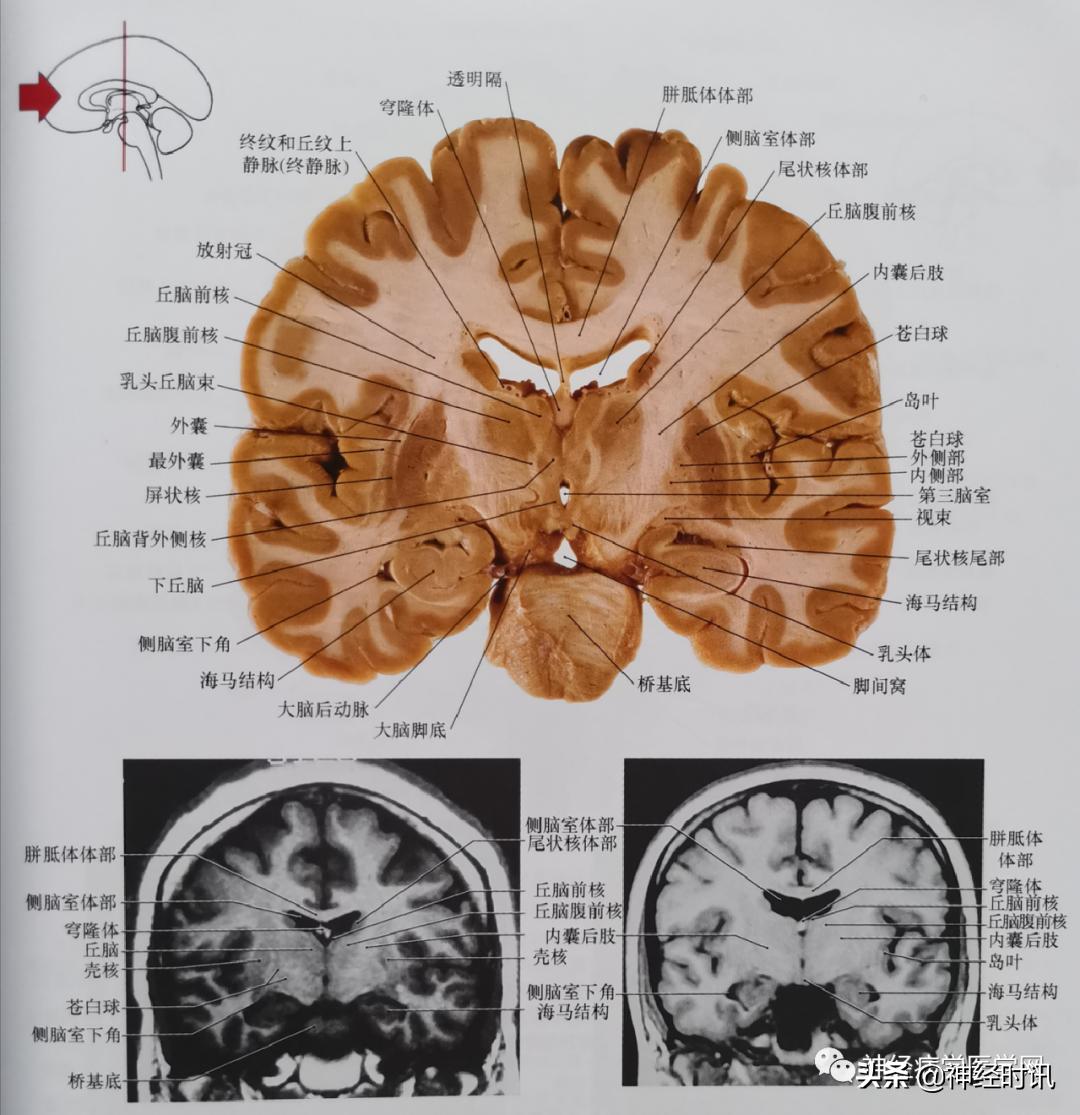

图4 通过丘脑前核、乳头丘脑束、乳头体平面的冠状位影像。此平面也包括桥基底(切片及磁共振影像可见)。这两张片子为相同平面磁共振影像(均为反转恢复技术),可显示许多切片上确认的解剖结构。苍白球在切片中清晰地分为内、外侧两段。此外,终静脉亦称为丘纹上静脉。

图5 通过丘脑腹外侧核尾部、中间块、丘脑腹后外侧核、红核、黑质、脑桥基底平面的冠状位影像。此平面儿完美地显示了内囊的纤维(切片中的内囊后肢)穿过大脑脚,进入桥基底(切片及磁共振影像可见);这些通过大脑脚的纤维,包括皮质脊髓纤维、皮质脑桥纤维(顶桥、枕桥、颞桥、额桥)及皮质核束纤维。